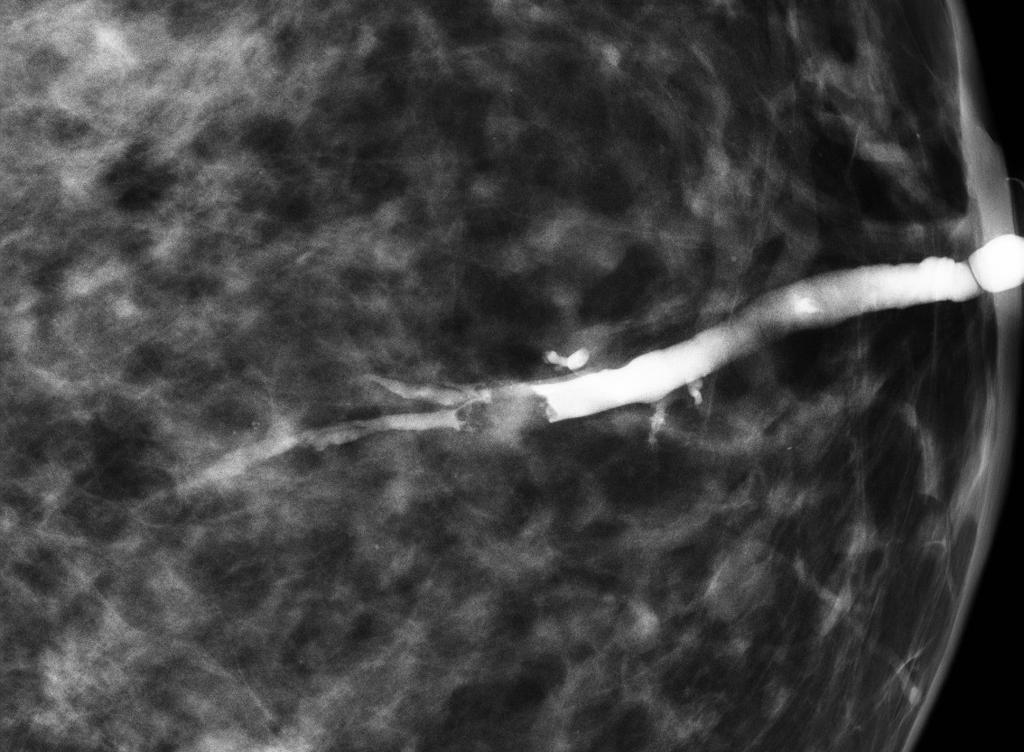

Linear, thick, ‘rod-like’ calcifications in both breasts, with a symmetrical distribution. Typical appearance of plasma cell mastitis (BI-RADS 2, benign).

Predominantly fatty breast tissue. No further findings.

Mammography

Plasma cell mastitis has a characteristic appearance. Calcifications are thick, linear, rod-like or cigar-shaped. Calcifications can be up to 10 mm long. They tend to be bilateral, often symmetrical in distribution and oriented with long axes pointing toward the nipple1. Branching may sometimes be seen.

Compared to microcalcifications of DCIS or ductal carcinoma, calcifications of plasma cell mastitis are larger in both length and caliber and have a smoother outline.